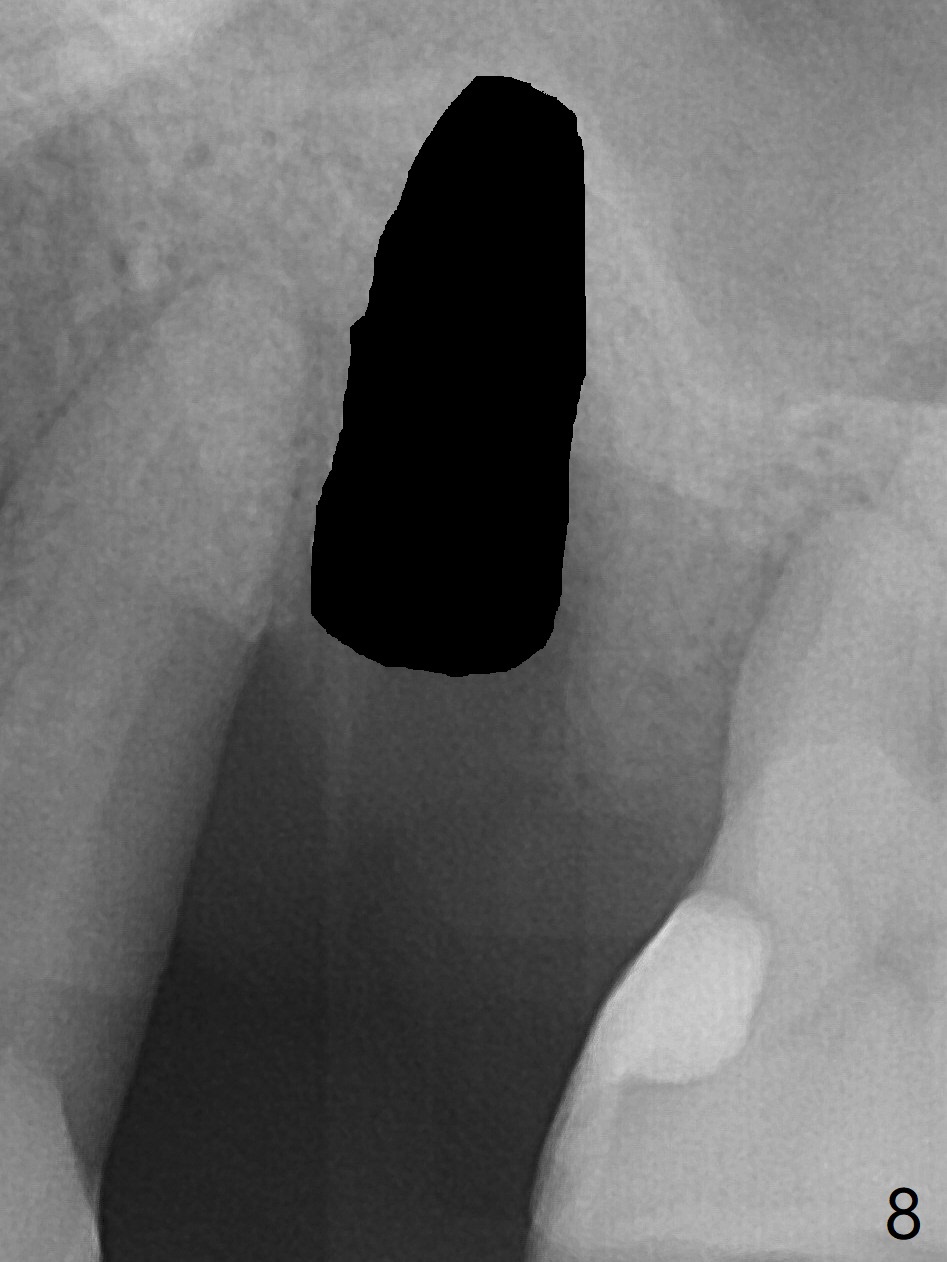

There is more bone apical to the residual root at #13 (Fig.1 red line). An immediate implant along the long axis of the root can be longer, 11.5 mm, favorable for primary stability (Fig.2 (CT taken immediately preop)). The initial trajectory is not ideal (Fig.3). When the pointed/Lindamann bur is removed (Fig.4), effort is made to move the apical end of the osteotomy distal (Fig.5 red arrow) by removing the apical bone (red dashed line). Following sequential osteotomy, a 4x10 mm dummy implant is placed with the trajectory remaining not so ideal (Fig.6,7). As the dummy implant is removed (Fig.8), a new osteotomy is established distal to the existing one (Fig.9). Subsequent drills gradually shift into the original osteotomy (Fig.10 red arrow). When the same dimension dummy implant returns, the trajectory improves with decreased stability (Fig.11). It seems reasonable to place a larger implant without further osteotomy. After placing PRF membrane and Vanilla graft for sinus lift (Fig.13 *), a 4.5x10 mm definitive implant is placed with loss of control in the trajectory (Fig.12,13).